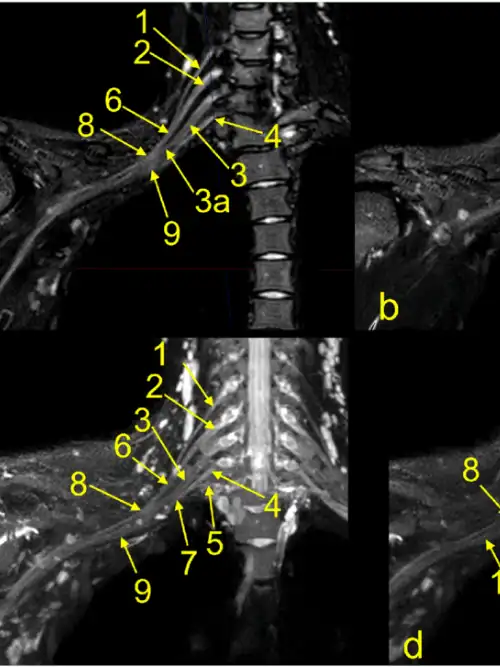

1. MRI scan

This will provide information about the number of nerves damaged, spinal cord injury and formation of a swelling in the covering of the spinal cord.

In BPI the nerve can be pulled our or disconnected from the spinal cord. The region where it gets disconnected undergoes scar tissue transformation and become a focus of pain generation. This region is called the “Dorsal Root Entry Zone” (DREZ), which is the first important level of modulation for pain and hence this area can be a target to treat resistant neuropathic pain in avulsion injuries.

The dorsal root entry zone (DREZ) lesioning procedure is a treatment for severe pain caused by nerves that have been torn away (avulsed) from the spinal cord. The procedure itself involves a neurosurgeon entering the spinal cord and causing multiple lesions in that damaged areas of pain generation from the spinal cord. Dr G Balamurali is among the very few Surgeons in the Country who has vast experience in performing this procedure under neuromonitoring. We have a 80% success rate.